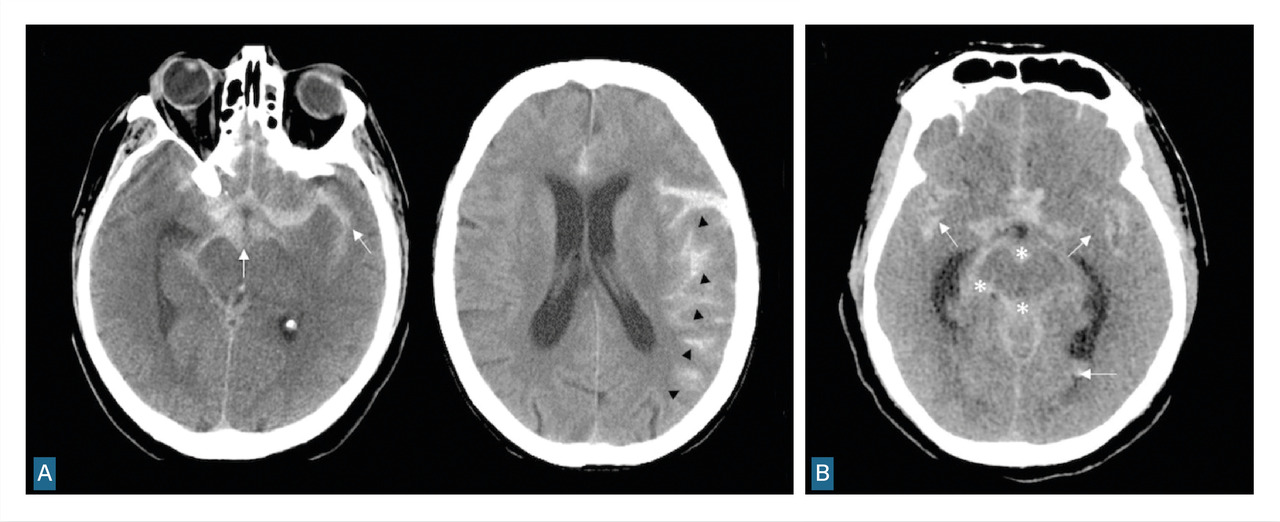

Le scanner doit être réalisé en urgence. Il montre une hyperdensité des espaces sous-arachnoïdiens, évalue la sévérité par l’échelle de Fisher et recherche les complications précoces (fig. 1 et tableau 1).

L’angiographie digitale permet de planifier et de suivre le traitement lorsqu’il est réalisé par voie endovasculaire. (fig. 4)